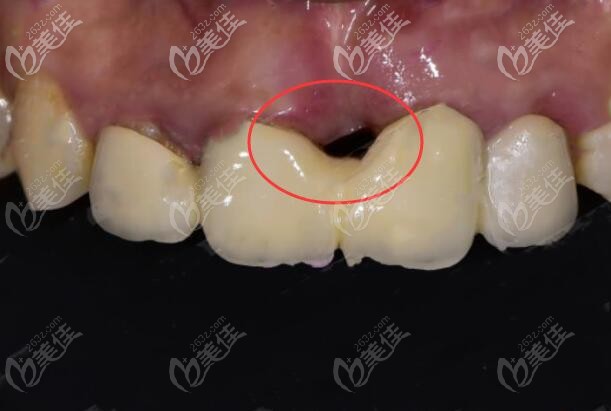

种牙后这么大的黑洞,要是我非哭死不可▼

事后我不由感叹,做种植牙,一定要多咨询几家医院,选择一个靠谱的医生,否则,后果不堪想象!